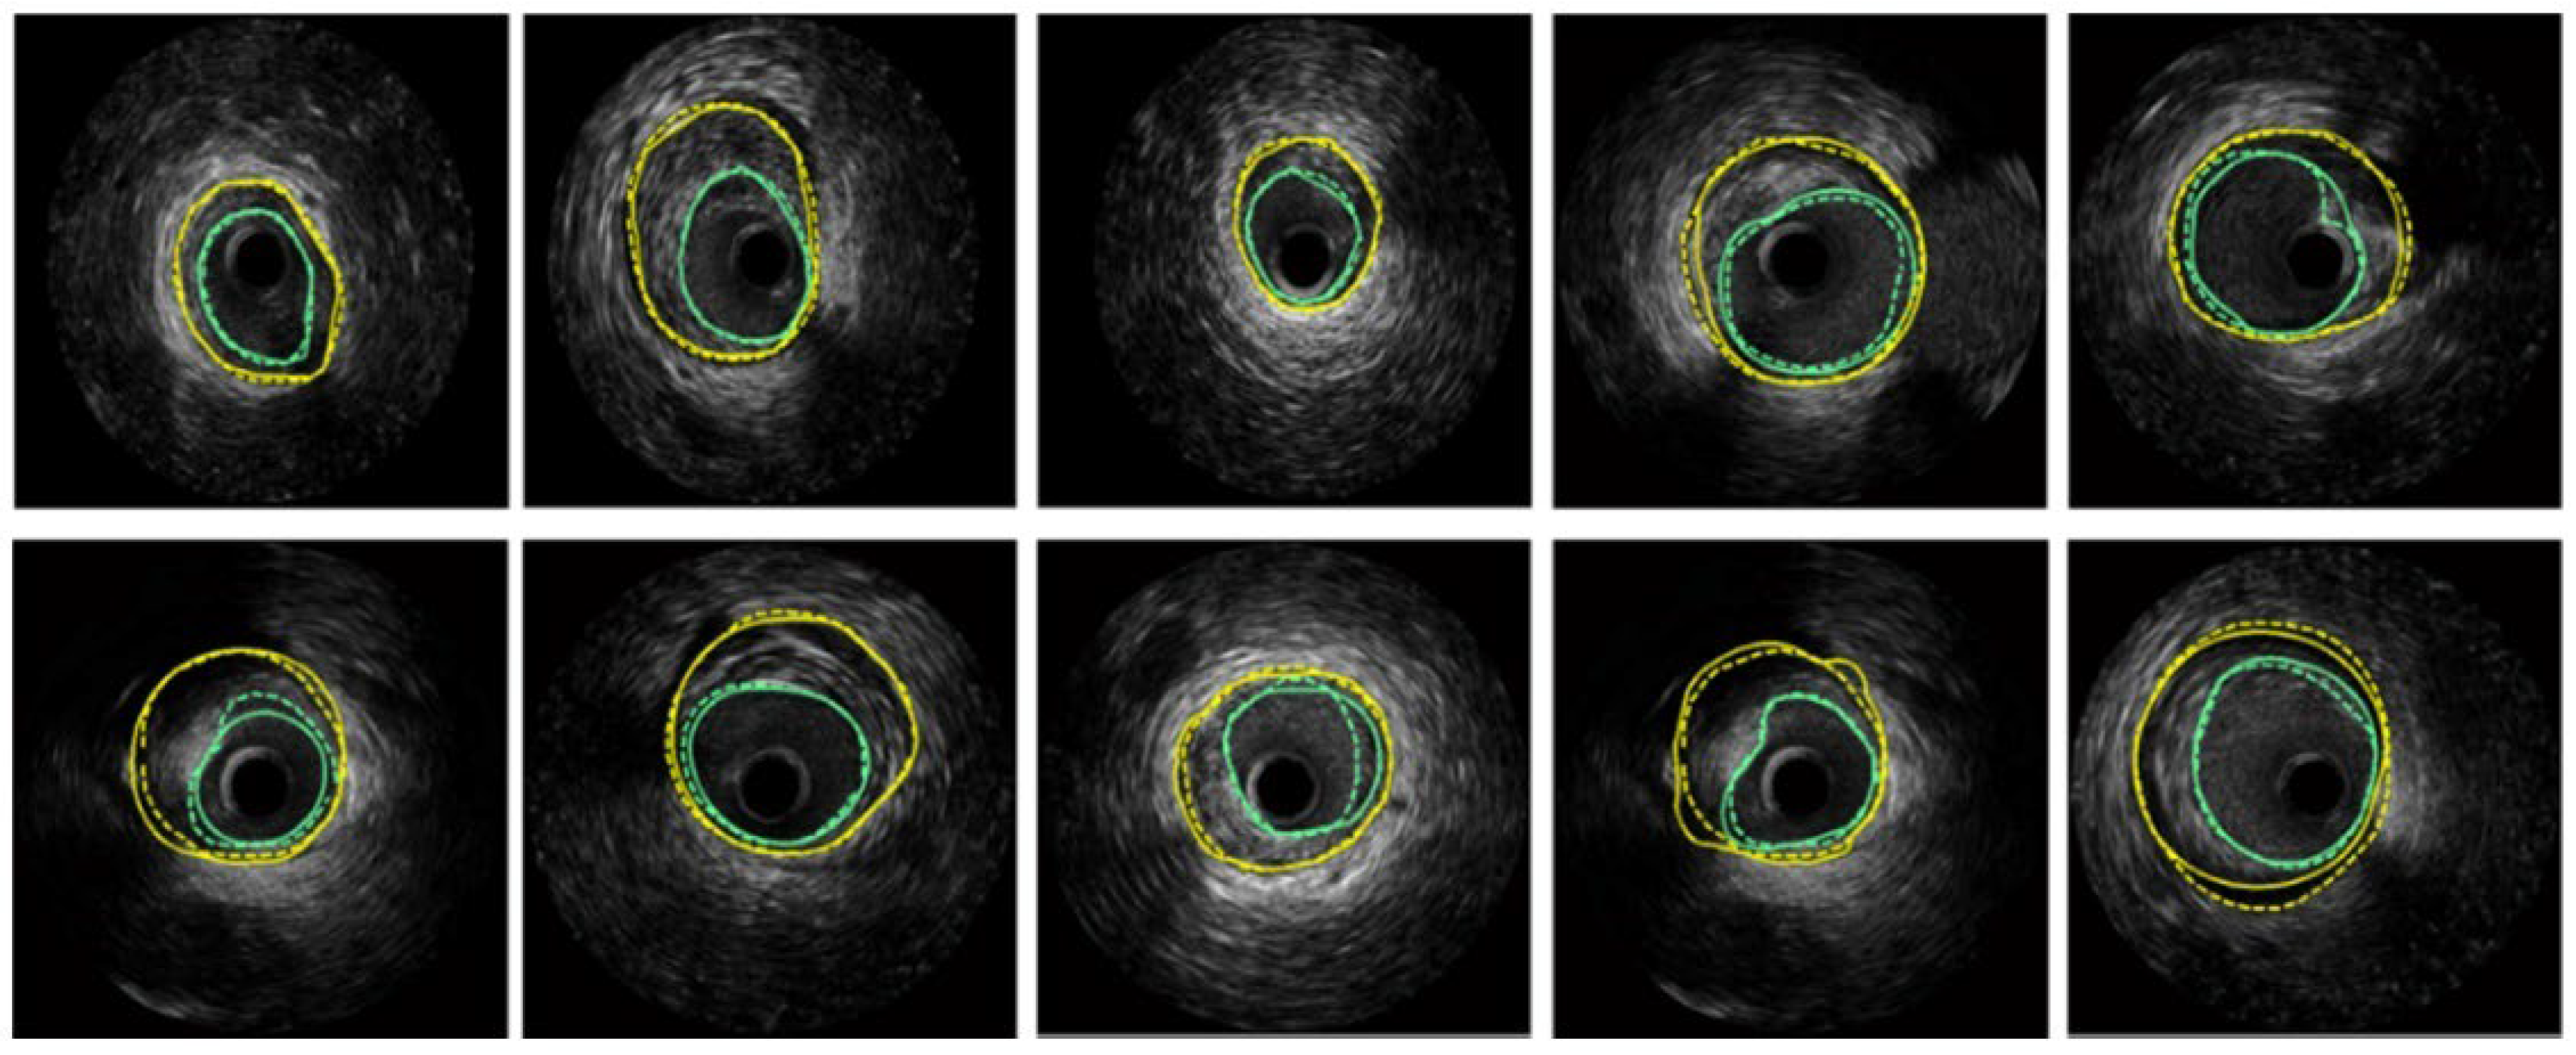

Figure 8.

Segmentation of several IVUS frames [70], showing the lumen boundary (green) and media-adventitia (MA) boundary (yellow). Solid lines represent ground truth annotations, while dotted lines indicate predicted segmentations from the model.